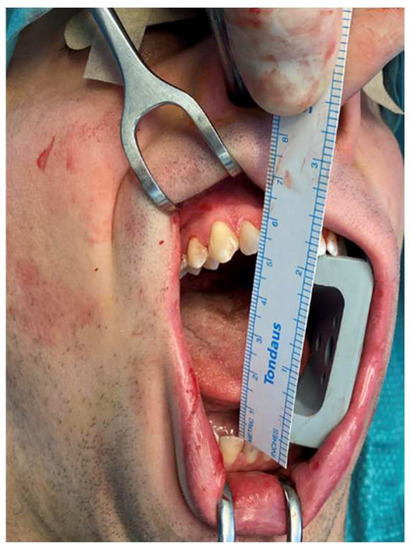

Figure 8.

Surgical sequence of the intraoral coronoidectomy. The patient shows an immediate improvement in the MMO up to 40 mm.

An 18-year-old male patient with a 24-month history of worsening reductions in mouth opening was referred to our attention for an evaluation of suspected TMD. No previous history of trauma was reported by the patient, and the medical history did not report any relevant elements. A physical examination showed an MMO of 20 mm with a deviation to the right during mouth opening (Figure 5). The patient did not complain of pain at the palpation of TMJ bilaterally. The masticatory muscles were painful bilaterally and especially on the right side. No TMJ clicking or crepitus were detectable. The endfeel was rigid and painful on the right side. At the OPG, the right glenoid fossa and condyle were not totally distinguishable, so an MRI and CT scan were requested to examine the case in depth. The MRI was negative for TMD, but in the CT scan, an enlarged right CPM with a mushroom-shaped end was highlighted, establishing a close relationship with the inner aspect of the right zygoma, which seemed impressed by the CPM forming a pseudojoint (Figure 6). It is interesting to notice how also the contralateral CPM was slightly elongated (Figure 7). The suspected diagnosis was of a right JD. The patient was subsequently submitted to an intraoral right coronoidectomy under general anesthesia. An incision along the vestibular aspect of the ascending mandibular ramus was performed, then a sub-periosteal dissection exposing the right maxillary zygomatic arch and the anterior rim of the mandibular ascending ramus was executed. At this point, the CPM was detected as showing a protuberance covered with fibrous tissue mimicking a capsule. Immediately after the completion of the coronoidectomy, the MMO increased to 40 mm (Figure 8). The histopathology of the CPM showed sections of compact, trabecular bone tissue covered by a layer of hyaline cartilage and fibrous cartilage overlaid by dense fibrous connective tissue—compatible with the diagnosis of osteochondroma (Figure 9). At 1 week, postoperative jaw-opening exercises and articular physiotherapy with TheraBite jaw motion rehabilitation system TM (Atos medical, Padua, Italy) were prescribed. At 1 month follow-up, the patient had an MMO of 20 mm, 18 mm at 2 months and 10 mm at 3 months. The cause of this negative trend was initially identified as the fibrotic retraction of the intraoral scar of the surgical access. At 5 months follow-up, the MMO was 32 mm and increased to 38 mm 1 month later. At 12 months follow-up, the MMO was 44 mm. A control CT scan was conducted and showed no recurrence and no significant changes on the contralateral side.

JD is a rare condition in which an elongated CPM interferes with the inner surface of the zygomatic arch, establishing a pseudojoint. In our review, which represents, possibly, the widest review in the literature, we report a mean age of 28.7 years old (5–73), with a difference in the age of incidence of almost 10 years between the two genders (25.7 years-old for males and 35.4 years old for females). In 12 cases, it was not possible to trace back the age of diagnosis of JD. We collected the data of 71 males (61.2%) and 34 females (29.3%). Unfortunately, 11 patients’ genders were not reported. These data are in agreement with what was previously reported in the literature, as affecting mainly men between the second and fourth decade [6]. An overall prevalence of 0.5% has also been reported, but this data could be underestimated because the onset of symptoms, such as limited mouth opening, represents just the endpoint of a longer-term development [55]. The left side is reported to be the most affected [7], which is confirmed by our analysis, in which we identified 38 cases of right JD (32.8%), 50 of the left side (43.1%) and 21 bilateral cases (18.1%). For seven cases, we were unable to retrieve information about the side of the defect. As mentioned before, JD usually remains relatively asymptomatic in its first stages, with most patients reporting only a sensation of tension during chewing. Then, it usually evolves with the limitation of mandibular movements and worsening reduction in MMO. In the reviewed cases, the mean MMO before surgical treatment was 13.9 mm (2–51). Sometimes, a distortion in the zygomatic arch projection on the affected side or a palpable moving hard mass perceptible during mandibular movements are present, particularly if JD is caused by an osteochondroma [94]. In unilateral cases, deviation to the affected side during mouth opening can be seen [75]. Pain or paresthesia are not often reported. This insidious clinical onset may be confused with several disorders such as TMD mainly, trauma arthrosis and various other causes of intra- and extra-articular ankylosis. Therefore, JD is also often mistreated. The etiology of the disease has already been widely debated. Some authors theorize a genetic or endocrine cause, and others suggest a role for temporalis muscle hyperactivity, trauma, TMJ disc displacement or a family predisposition, but it is mostly considered idiopathic [3,52,112]. Although the cause remains unknown, some authors reported periosteal hyperactivity as a trigger for ectopic metaplastic cartilage formation [5]. As stated before, according to the different amounts and patterns of bone and cartilage tissues present, the abnormally enlarged CPM can be histologically diagnosed as OC, CCE, CH, benign tumors (such as osteoma or chondroma) or other developmental anomalies [4,7,10,14,70]. We found 17 cases of CCE (14.7%), 10 cases of CH (8.6%) and 76 cases of OC (65.5%), while in 13 cases (11.2%), it was not possible to establish a definite histological diagnosis. This marked prevalence of OC as a cause of JD may partly explain the confusion over its definition and its almost exclusive bi-directional association with pathology reported by various authors. It is also interesting to note how this pathology shows different clinical and radiological patterns, leading to a wide spectrum of presentations. Considering, for example, the cases we have reported, it is possible to see how they present a pattern of increasing severity from the first to the third patient. The first patient presented an early pathologic radiological pattern, with the pseudojoint not yet fully formed with an MMO of 25 mm. It should be remembered that ankylosis, in this case, extra-articular, is established when the MMO is less than 15 mm, and this is considered an incomplete ankylosis, when the MMO is less than 5 mm, the ankylosis is complete [113,114]. In contrast, the second patient showed a well-established ipsi-pseudo-articular framework and an MMO of 20 mm. In this patient, it is also interesting to notice how the contralateral CPM was also slightly longer than normal, although not yet pathological. The third patient, on the other hand, showed a well-established bilateral pattern with perfectly developed pseudojoints and a rapidly worsening 20 mm MMO. Our experience and analysis of the literature prompted us to wonder whether it was possible to classify, according to clinical and radiological features, the vast pathological spectrum that JD expresses. We, therefore, designed a classification proposal, as shown in Table 2, in order to speculate on the possibility of assigning an index of severity and stage to the various connotations of JD. Obviously, this classification has to be intended as a proposal, considering that more cases have to be analyzed to evaluate its possible validity.